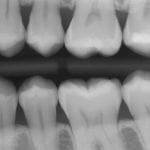

DIGITAL X-RAYS

Digital radiographs with exquisite detail and dramatically reduced radiation exposure offer the ultimate in safety and diagnostic capability.